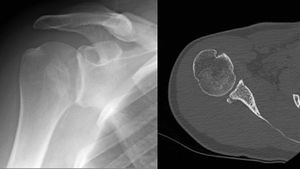

A2

Left) X ray of a first-time posterior dislocation. Right) Computed tomography image a posterior fracture without reverse Magaigne (Hill-Sachs) lesion.